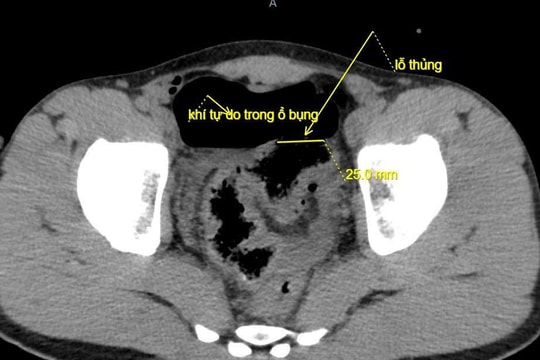

Hy hữu: Trêu đùa bằng vòi xịt rửa xe gây thủng đại tràng

20/10/2025 14:59

Một trò đùa thiếu an toàn khiến nam thanh niên bị thủng đại tràng, phải phẫu thuật cấp cứu để giữ tính mạng.